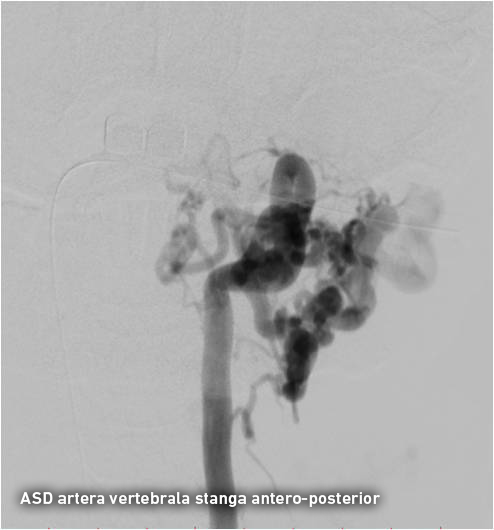

Pentru precizarea diagnosticului a fost nevoie de o investigație invazivă și anume angiografia cu substracție digitală a vaselor capului și gâtului, ce reprezintă „standartul de aur “ în patologia neurovasculară. Angiografia clasică diagnostică a confirmat existența unei fistulei arterio-venoase posttraumatice cervicale pe stânga și ocluzia venei jugulare stângi. Fistula arterio-venoasă posttraumatică reprezintă comunicarea anormală dintre sistemele venos și arterial apărută după leziunea peretelui vascular. În cazul dat sângele arterial din artera vertebrală stângă și trunchiul tireo-cervical stâng pătrundea sub presiune înaltă în porțiunea incipientă a venei jugulare stângi, apoi retrograd în sinusul sigmoid stâng, sinusurile transverse, sinusul sigmoid drept și se drena extracranian prin vena jugulară dreaptă. Arterializarea sângelui din sinusurile venoase ale durei mater are ca consecință creșterea presiunii venoase intracraniene, apariția stazei venoase și dilatarea venelor cerebrale superficiale și profunde. Ca rezultat, bolnavii cu fistule arterio-venoase a vaselor precerebrale și cerebrale suferă de dureri de cap și de ochi, dereglări cognitive, afectarea nervilor cranieni (conflict neuro-vascular cu n. trigemen și n. facial) și acufene. Hipertensiunea venoasă intracraniană poate cauza accidente vasculare hemoragice, ce reprezintă una din cauzele principale de morbiditate şi mortalitate.

Tratamentul endovascular a fost realizat grație colaborării multidisciplinare între neurochirurgul-intervenționist Alexandru Șumleanschi, cardiologul-intervenționist Eugen Calenici și neuro-anestezisteziolog Iana Cotorcea. Embolizarea a avut loc în 2 etape sub anestezie generală : pe 15.07.2016 a fost ocluzată artera cervicală ascendentă stângă (trunchiul tireo-cervical) cu Onyx și pe 02.09.2016 a fost realizată ocluzia arterei vertebrale stângi (segmentul V2-V3). Toate obiectivele propuse înainte de operație au fost realizate cu succes. Starea pacientului s-a ameliorat după embolizare: au dispărut acufenele, au diminuat durerile nevralgice, ceea ce a permis diminuarea tratamentului neurotrop. Spre deosebire de chirurgia clasică, pacientul a necesitat timp redus de spitalizare și recuperarea după embolizare a fost rapidă.